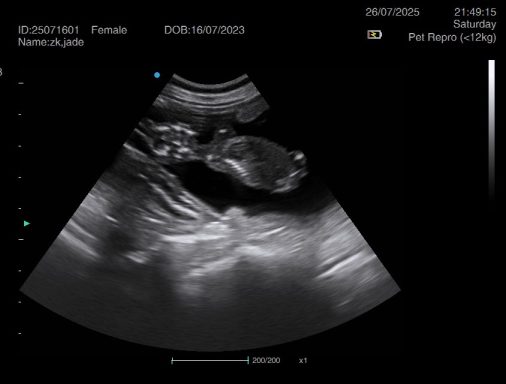

Ultrasound pregnancy scanning is a safe, non-invasive way to confirm pregnancy in dogs and cats, offering breeders and pet owners peace of mind and vital information to support responsible care. It allows us to detect gestational sacs, assess foetal development, and estimate litter size—all while ensuring the wellbeing of the animal.

Pregnancy can sometimes be detected as early as Day 18 post-mating, but scanning at this stage is not routinely recommended. Embryos are still developing and may not be clearly visible, and there is a natural risk of embryo resorption, which can lead to misleading or inconclusive results.

For the most accurate and reliable scan, we advise booking between Day 25 and Day 32, when pregnancy is more easily confirmed and foetal structures are clearer. If an early scan is performed and no pregnancy is detected, we offer a FREE complimentary re-scan after 7 days at the clinic to ensure clarity and support informed decision-making.

Our approach balances early insight with ethical care—always prioritizing the comfort of the animal and the accuracy of the results.

Gallery